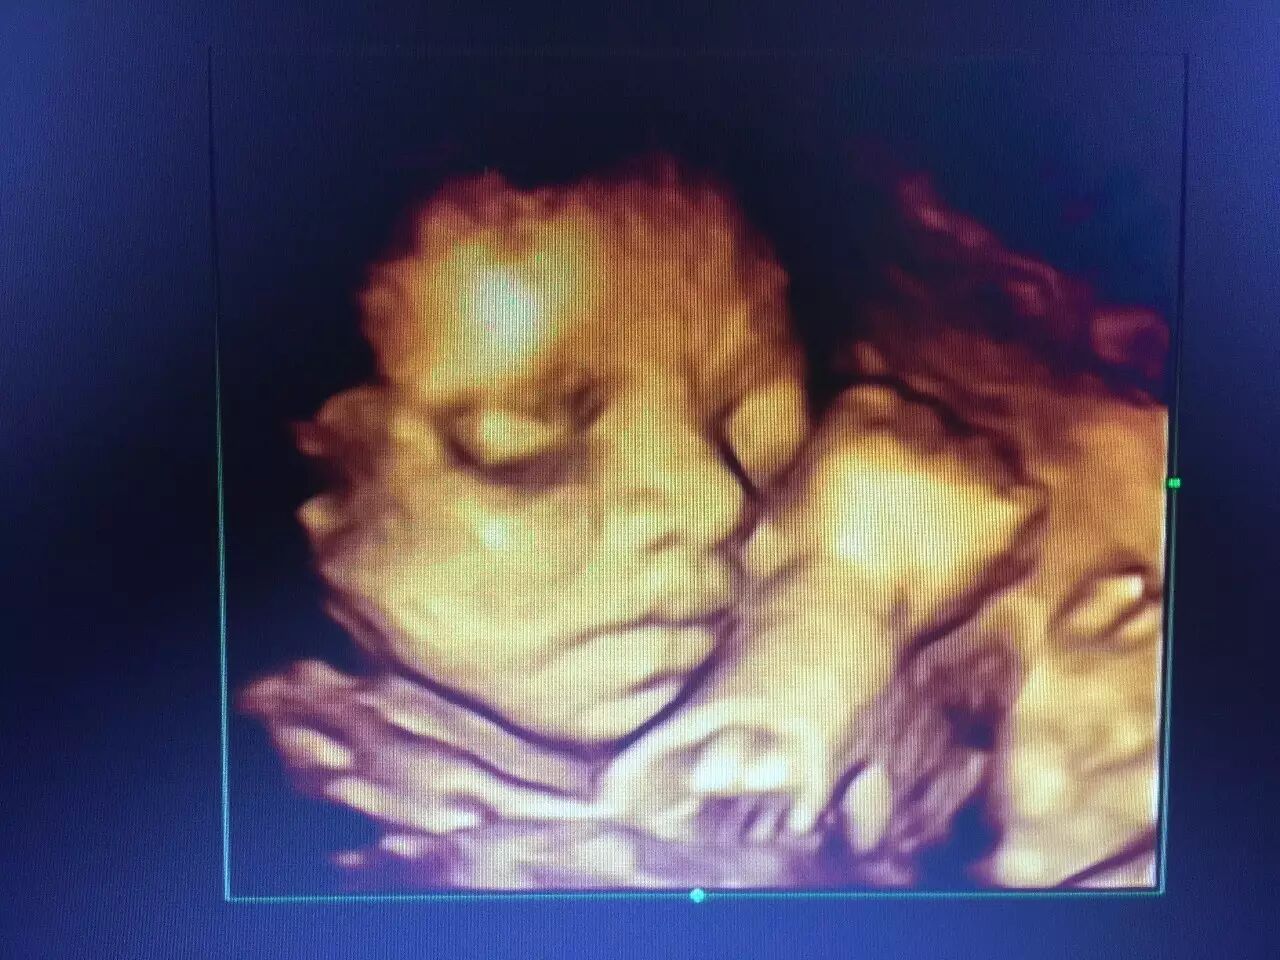

其优点一改既往二维超声中黑白色调的静态平面图像,而变成有色彩的立体动态的人体器官(包括胎儿)的实时活动图像,使医生的诊断更精确、可靠

排查胎儿发育是否畸形,可以清楚的看到孩子的发育情况,除了能看到孩子的五官发育,四肢发育以外,内部心脏,肾脏发育,脊柱发育,脑部发育四维彩超也能清楚的看到。